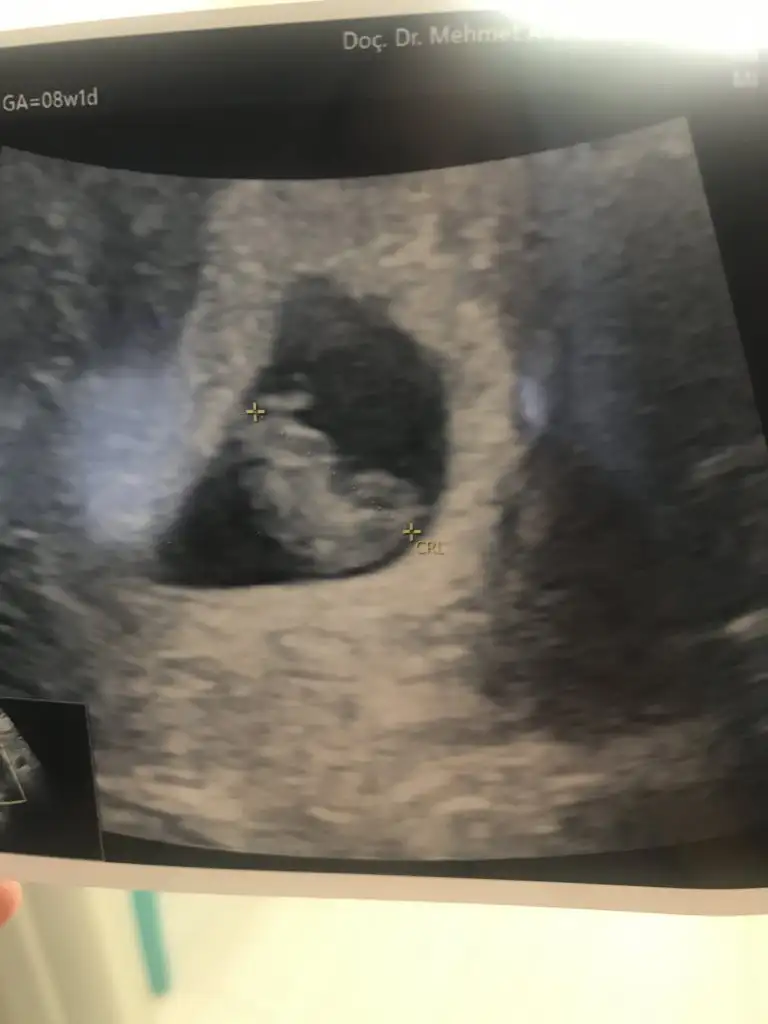

Bu da bizim 9 hafta karindan ultrason anlayan beri gelsin🤩😂

Kızlaaaarrr biliyorum saçmaliyoruz ama napalim merak ediyoruz